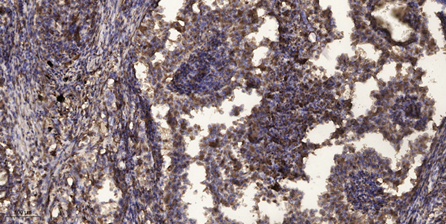

Immunohistochemical analysis of paraffin-embedded human Squamous cell carcinoma of lung.